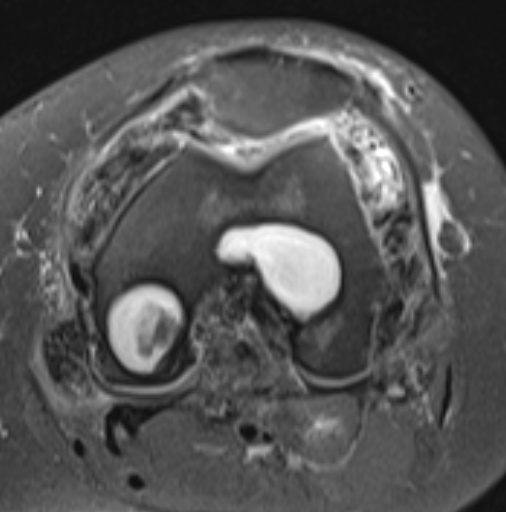

MRI

Synovial thickening

Hemosiderin

- low signal intensity on TI and T2 - "drop out" signals

- blooming on gradient echo

Diffuse

Diffuse PVNS with involvement of suprapatella pouch and posterior compartments, including posterior extra-articular

Severe diffuse PVNS with bony involvement